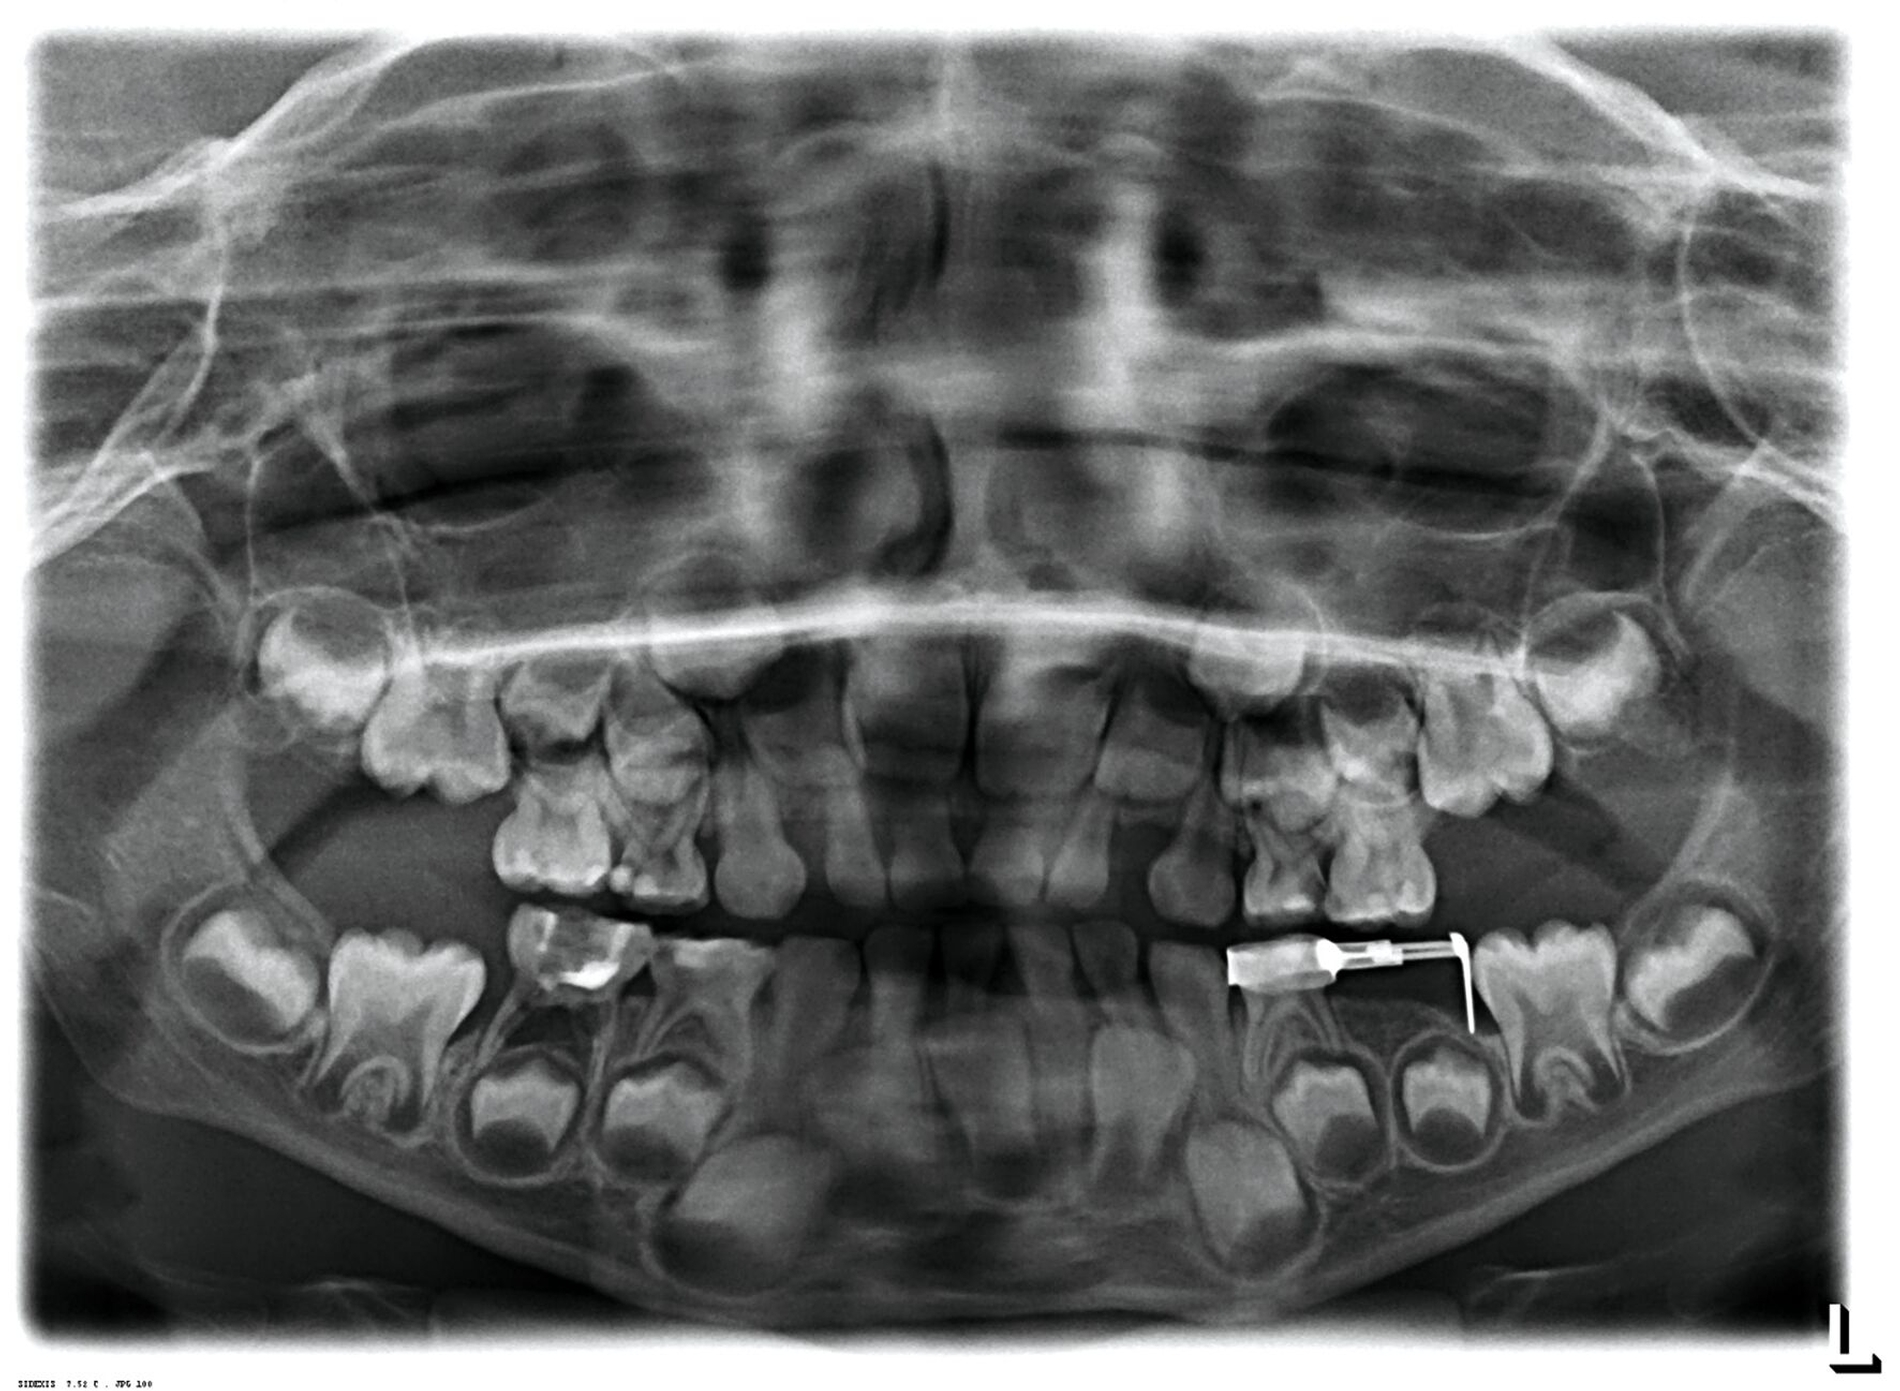

Zentrales Problem bei der Milchgebisskaries ist aber nicht dieser Mineralverlust oder der Defekt, sondern die „übergroße“ Pulpa, die häufig mit betroffen ist (Abbildung 2), bei oftmals zugleich geringer Kooperationswilligkeit oder -fähigkeit der Kinder für invasive Eingriffe. Damit ist bei kariösen Defekten an Milchzähnen die korrekte Diagnose zum Zustand der Pulpa beziehungsweise die Abschätzung der Pulpabeteiligung der kariösen Läsion die primäre und wichtigste Aufgabe. Dies ist allerdings bei Kleinkindern über die Schmerzanamnese und die Röntgenbilder häufig nicht valide möglich. Es gibt zwei Möglichkeiten, dieses Dilemma zu lösen:

Alle irreversiblen Pulpitiden oder gar Pulpanekrosen bedingen eine endodontische oder eine Extraktionstherapie des Milchzahns. Bei beiden Ansätzen sind der kariöse Defekt, seine Ausdehnung oder die Kariesentfernung das eindeutig sekundäre Problem, die Kooperation des Kindes bei diesen Maßnahmen ist dafür umso entscheidender. Im Folgenden sollen diese einzelnen Therapiepfade detaillierter dargestellt werden.

Eine weitere wichtige Alternativmethode ist die Hall-Technik [Santamaria and Innes, 2018; Midani et al., 2019; Santamaría et al., 2020], die im Rahmen neuer biologischer Konzepte bereits vor einigen Jahrzehnten von Dr. Norna Hall in Schottland entwickelt wurde. Im Gegensatz zur konventionellen Stahlkronenversorgung wird bei dieser Technik auf Lokalanästhesie, Präparation und Kariesentfernung vollständig verzichtet. Stattdessen wird eine vorgefertigte Stahlkrone direkt auf den kariösen, pulpal asymptomatischen Milchmolaren zementiert (Abbildung 7). Die Hall-Technik hat in vielen klinischen Studien gezeigt, dass die klassische „Kariesentfernung“ nicht nötig ist, wenn die Restauration bakteriendicht und stabil platziert werden kann. Darüber hinaus gibt es SMART-Techniken (Silver Modified Atraumatic Restorative Technique), die die Anwendung von SDF mit minimalinvasiven restaurativen Verfahren wie der ART oder der Hall-Technik kombinieren. Bei der SMART-Technik wird nach der Kariesarretierung mit SDF entweder eine hochviskose Glasionomerzementfüllung (SMART) oder eine vorgefertigte Stahlkrone (SMART-Hall, Abbildungen 5b und 5c) eingesetzt. Diese Kombination verbessert die Prognose des Zahnes, vermeidet mögliche Frakturen und Platzverluste und trägt ästhetisch-funktionellen Ansprüchen besser Rechnung.

Minimalinvasive Behandlungsmethoden wie die ART, die Hall-Technik (HT) und die SMART-Technik stellen kindgerechte, nicht-invasive, evidenzbasierte und erfolgreiche Alternativen dar. Obwohl minimalinvasive Verfahren zunehmend bevorzugt werden, bleiben konventionelle restaurative Techniken wie Stahl- und Stripkronen bei stark zerstörten Milchzähnen unverzichtbar. Sie stellen insbesondere bei ausgedehnten kariösen Defekten eine bewährte und dauerhafte Versorgung dar [Pötter et al., 2024]. Die Wahl der geeigneten Therapie und das Maß der Kariesentfernung muss immer individuell erfolgen, unter Berücksichtigung des Kariesausmaßes, des Behandlungssettings (chairside, Sedierung oder in Narkose), der Kooperationsfähigkeit des Kindes und der Langzeitprognose.

Trotz der zunehmenden Bedeutung minimalinvasiver Techniken bleiben etablierte restaurative Therapien weiterhin relevant und erfolgreich. Zu den bewährten Standardverfahren zählen insbesondere Stahlkronen mit konventioneller Präparation und Kariesentfernung. Sie stellen nach wie vor eine stabile Lösung bei stark kariösen Milchmolaren und bleibenden Molaren im Wechselgebiss (zum Beispiel MIH-Zähne) dar. Stahlkronen sind besonders geeignet bei großen kariösen Defekten, nach endodontischer Behandlung, bei hoher Kariesaktivität, bei Frakturen oder bei Zahnfehlbildungen. Ihr vermehrter Einsatz beruht auf stabilen, langanhaltenden Behandlungsergebnissen. Darüber hinaus sind ästhetische Kronen (zum Beispiel Stripkronen) ideal für Milchfrontzähne mit hohem ästhetischem Anspruch. Diese Technik erfordert jedoch präzises Arbeiten und eine gute Feuchtigkeitskontrolle. Sie ist besonders geeignet bei stark betroffenen Frontzähnen (mit inaktiven mehrflächigen Läsionen), bei Beteiligung der Schneidekante, nach einer Pulpatherapie sowie bei hohem Kariesrisiko.

Bei ausgedehnter Karies und vor allem bei pulpaler Beteiligung bietet das Milchgebiss als Übergangsdentition den Vorteil, dass eigentlich nur der Platz für den bleibenden Zahn bis zu dessen Durchbruch gehalten werden muss. Zahnerhaltung ist damit in der Kinderzahnheilkunde nicht das oberste Gebot. Gerade Milchfrontzähne, die häufig früh und schwer von frühkindlicher Karies betroffen sind, haben keine Platzhalterfunktion und die permanenten Ersatzzähne brechen schon mit der Einschulung durch. Die kariösen Defekte können damit ausreichend, wirtschaftlich und zweckmäßig gleich „mit dem ganzen Zahn“ entfernt werden. Auch bei Milchmolaren ist bei Betrachtung der Zahnebene die Extraktion eine schnelle, einfachere, erfolgreichere und günstigere Therapie als eine Pulpotomie, eine Pulpektomie und die finale Stahlkrone. Der frühzeitige Verlust von Milchmolaren birgt aber das Risiko eines sekundären Engstands und einer nachfolgenden kieferorthopädischen Behandlung, gegebenenfalls sogar mit einer Extraktion von Prämolaren. Daher muss zwingend mit der Extraktion ein Konzept des Platzmanagements erstellt und parallel umgesetzt werden (Abbildung 8).